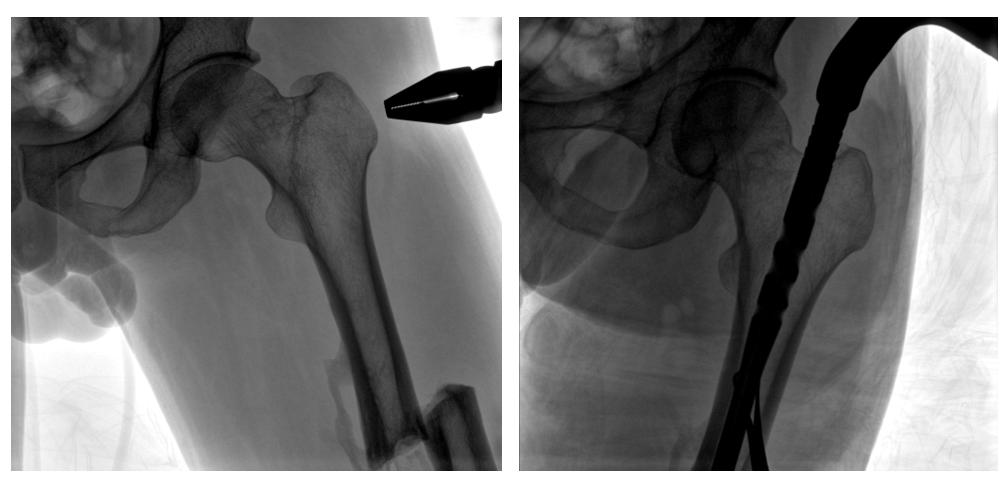

The patient had a complete fracture of the left femoral shaft, which was treated with "intramedullary nailing and internal fixation" after evaluation by the doctor. Intramedullary nail fixation needs to fully display the image from the nail insertion point to the fracture site. In some long bone fractures, the field of view is required to be high.

When performing intramedullary nail fixation, the doctor needs to observe the nail entry point and the fracture site at the same time. The PLX119C large flat-panel integrated C-arm can present a wider imaging area, which is suitable for most long intramedullary nail fixation. photography needs.

In conclusion, the large-plate integrated C-arm can obtain a larger field of view and a clearer image of the fracture site in orthopaedic surgical treatment of spine and long bone fractures, which can help doctors to understand and evaluate the alignment and evaluation of the fracture site in time during surgery. Alignment, and can measure length and angle, providing strong support for further improving the quality of surgery